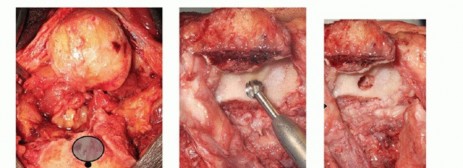

TECH FIG 4 •(continued)I-K. Latitude DHH. I. Intact medial and lateral humeral columns, with a red vessel loop loosely around the ulna nerve. J. AP radiograph demonstrating the trochlea and capitellum correctly sized for the host, greater sigmoid notch of the ulna, and the radial head. K. Lateral radiograph demonstrating a well-aligned radio capitellar joint and osseous integration of the anterior flange. L-N. Sorbie DHH. L. Fractured medial and lateral columns were reconstructed with K-wires, prior to implant insertion. M. AP radiograph demonstrating a well-seated Sorbie implant with healed medial and lateral columns. N. Lateral radiograph demonstrating a well-aligned radiocapitellar joint with posterior heterotopic ossification in the traumatically injured triceps muscle.